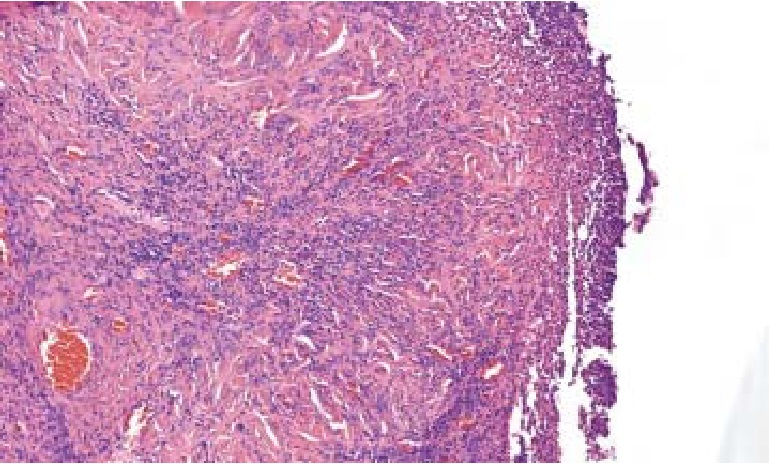

Наибольшая степень выраженности ранних процессов репаративной регенерации констатирована в группе животных, где после некрэктомии выполнялась аппликация раневых покрытий на основе БЦ с фукоиданом. Гистологически на 14-е сутки в этой группе животных определялся дефект, покрытый фибринозным экссудатом, густо инфильтрированным нейтрофильными лейкоцитами. Под фибринозными пленками наблюдается грануляционная ткань, в которой преобладают лимфоциты и макрофаги, очагово отмечаются крупные лейкоцитарные инфильтраты. В подлежащих слоях обнаруживается незрелая соединительная ткань со значительным количеством мелких фибробластов и новообразованных сосудов капиллярного типа, что позволяет заключить о положительном влиянии раневых покрытий на раннюю фазу раневого процесса, пролиферативную активность фибробластов, синтез ими внеклеточного тканевого матрикса (рис. 4).

Рис. 4. Гистологический срез биоптата раны в зоне ожога кожи III степени после ранней некрэктомии, аппликации покрытий на основе БЦ толщиной 1–2 мм с фукоиданом, 14-е сутки наблюдения. Незрелая соединительная ткань со значительным количеством мелких фибробластов и большим количеством новообразованных сосудов. Окраска гематоксилин-эозином, ув. ×200